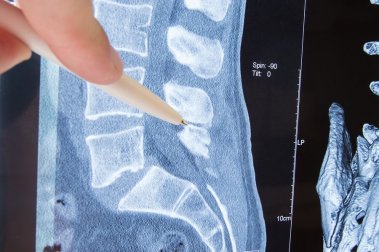

A coluna vertebral é uma estrutura óssea formada por vértebras que, por sua vez, protegem a medula óssea e nos permitem circular livremente sem maiores dificuldades. As vértebras têm orifícios em cada um dos lados, dos quais saem os nervos que vão para as diferentes partes do corpo.

A parte do nervo que sai da vértebra é chamada de “raiz nervosa”. Uma radiculopatia é a compressão do nervo, mais precisamente da raiz do nervo. Quais são as suas causas? Quais manifestações clínicas ela apresenta? Responderemos a estas perguntas a seguir.

Corresponde à coluna lombar. Os nervos nessa área controlam os músculos e a sensibilidade da pele dos glúteos e dos quadris aos pés. Portanto, os sintomas da radiculopatia lombar costumam ser observados na região lombar, quadril, pernas e pés.

Nos casos mais graves, o controle dos esfíncteres fica comprometido. Se a compressão ocorrer na saída do nervo ciático, o sintoma mais comum é a dor da região lombar até a sola dos pés, passando pela parte posterior da perna. Isso é conhecido como ciática.